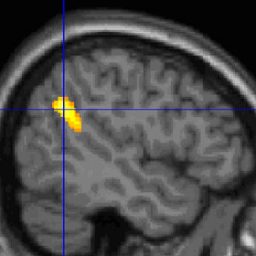

Почему мы помним свои сны?

Французские ученые обнаружили, что у людей, которые хорошо помнят свои сны, в коре мозга есть две области повышенной активности, которые работают как во сне, так и наяву.